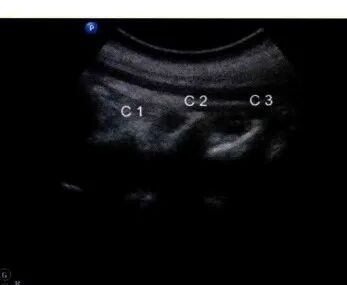

采用平面内技术,在选定的穿刺点,以长3.5英寸带芯穿刺针在超声探头的下方以小关节为靶点从尾侧向头端方向进针( 图9和图10 )。

图9 / 超声引导下颈椎小关节内阻滞